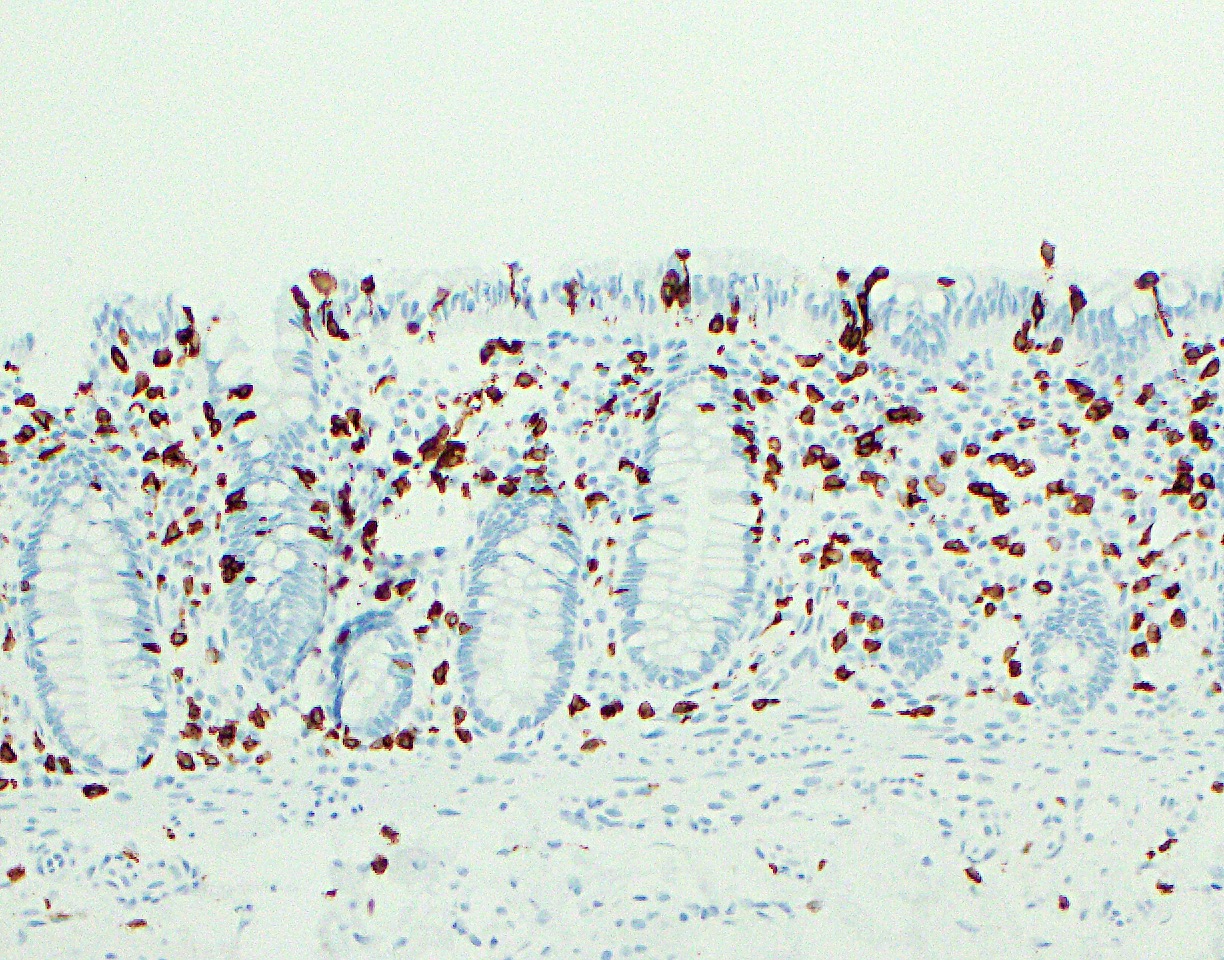

Positive stains

- Enterocytes (absorptive cells): pankeratin AE1 / AE3, CK20, CDX2, SATB2 and villin

- Enteroendocrine cells: synaptophysin, chromogranin, neuron specific enolase (NSE) and pankeratin AE1 / AE3

- Inflammatory cells:

- Lamina propria T lymphocytes: CD3+ / CD4+

- Intraepithelial T lymphocytes: surface - CD3+ / CD8+ and TCRαβ+; near lymphoid follicles - CD3+ / CD45RO+ (Chem Immunol 1998;71:1)